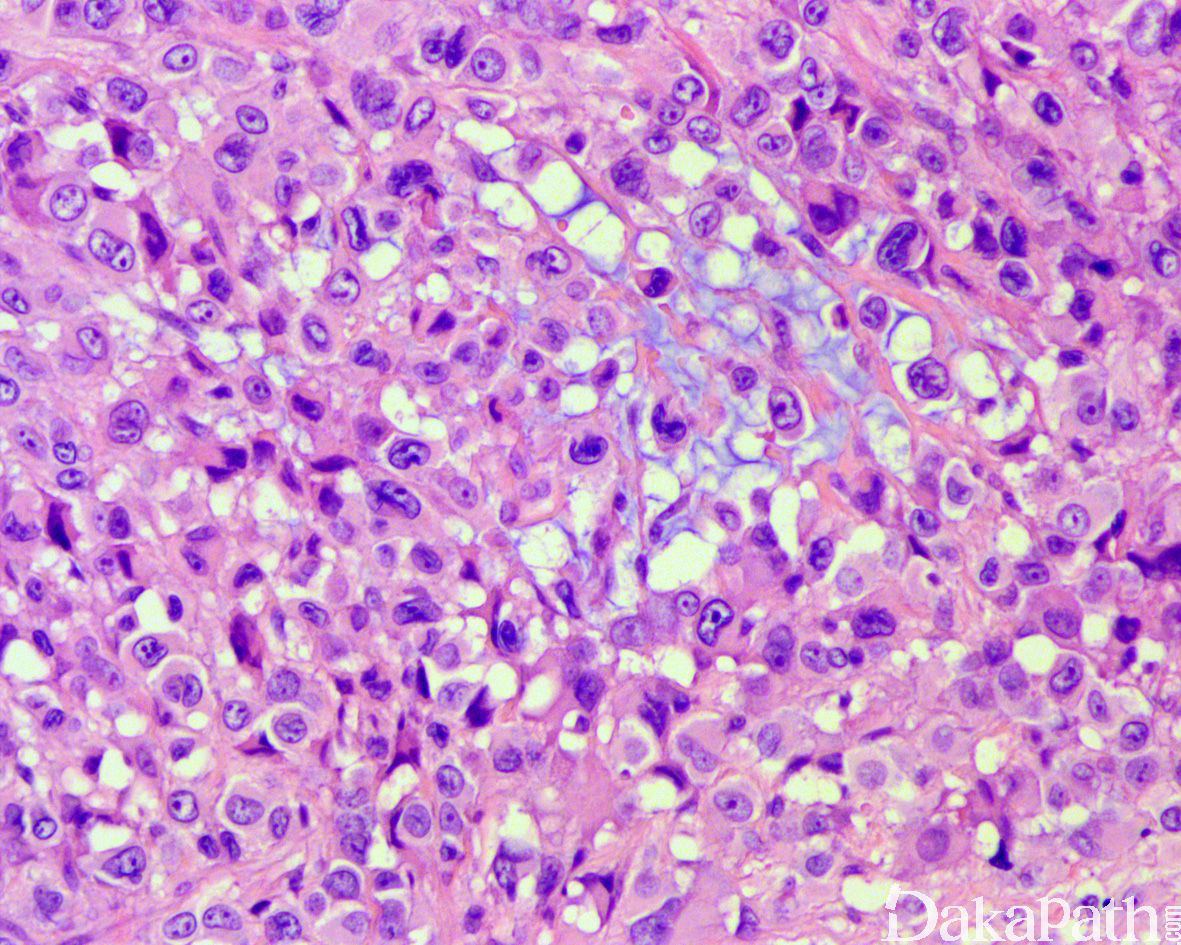

经典型:

瘤细胞呈结节状或花环样排列,结节周围围绕胶原纤维,结节中央常伴有坏死;

肿瘤由上皮样细胞和梭形细胞共同组成,上皮样细胞呈多边形、卵圆形或胖梭形,胞质丰富,深嗜伊红色,和梭形细胞间有移行;细胞核轻度异型,呈空泡状,可见小核仁,核分裂像通常少于 5/10HPF;

间质可见嗜伊红色的胶原纤维;

近端型:

呈多结节性,以上皮样细胞为主,梭形细胞少;

上皮样细胞大而圆,有明显的异型性,染色质呈空泡状,可见明显的核仁,常见坏死;

部分区域可见横纹肌样瘤细胞,当横纹肌样瘤细胞较多时,可称为具有横纹肌样上皮样肉瘤。